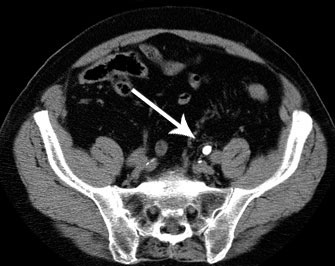

La revisión muestra que favorece la eliminación de cálculos de entre 5 y 10 mm de diámetro. Annals of Emergency Medicine, 8 de septiembre de 2016